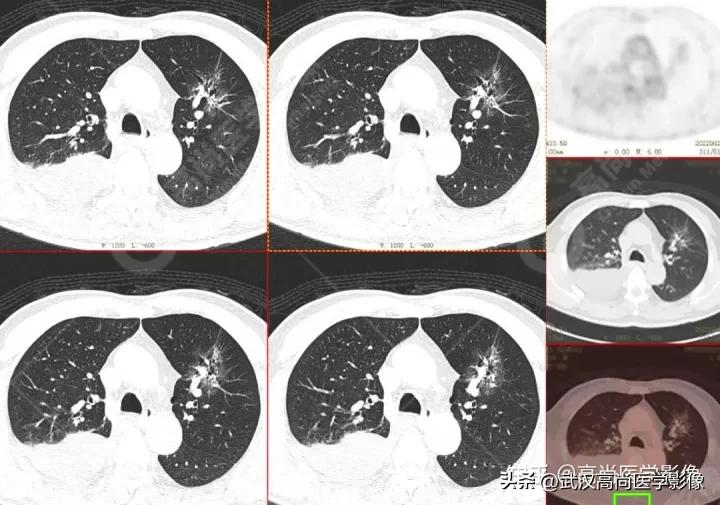

右肺下叶背段见一实性结节,大小约2.0cm×1.6cm×1.8cm,CT值33Hu,FDG高摄取,SUVmax13.0。

恶性CT征象:

病灶边缘分叶、短毛刺,其近端亚段支气管截断,瘤肺界面清楚,病灶远端片絮状阻塞性炎症。

右肺上叶尖段胸膜下见一实性结节,范围约1.6cm×1.3cm,病灶紧贴邻近胸膜,伴牵拉增厚,FDG高摄取,SUVmax为7.5。

结节边缘不光整,分叶、长短不一的毛刺,邻近胸膜牵拉明显。

另外,左肺上叶前段见一团状混杂磨玻璃影,范围约4.3cm×3.3cm,CT值约-662Hu,内部扭曲扩张支气管及血管影穿行,边缘分叶、棘状突起,FDG摄取轻度增高,SUVmax1.3,考虑为多中心起源浸润性肺癌(多原发的肺癌)。